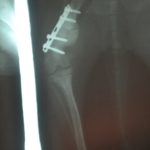

She had a pronounced limp and on performing x-rays our veterinarian found that the femur has grown a long spike that had extended and was now impinging on the knee cap in the attempt to ‘close the space’. Vale was in a great deal of pain from this and the vet performed a surgery to cut the point off, re-break the bone, and plate the fracture so it will heal (and hopefully grow) properly. The plate may have to be removed in about three months, so Vale is not really available for adoption until we know if the plate will stay or not.

Vale had her surgery on December 29th and is healing beautifully.